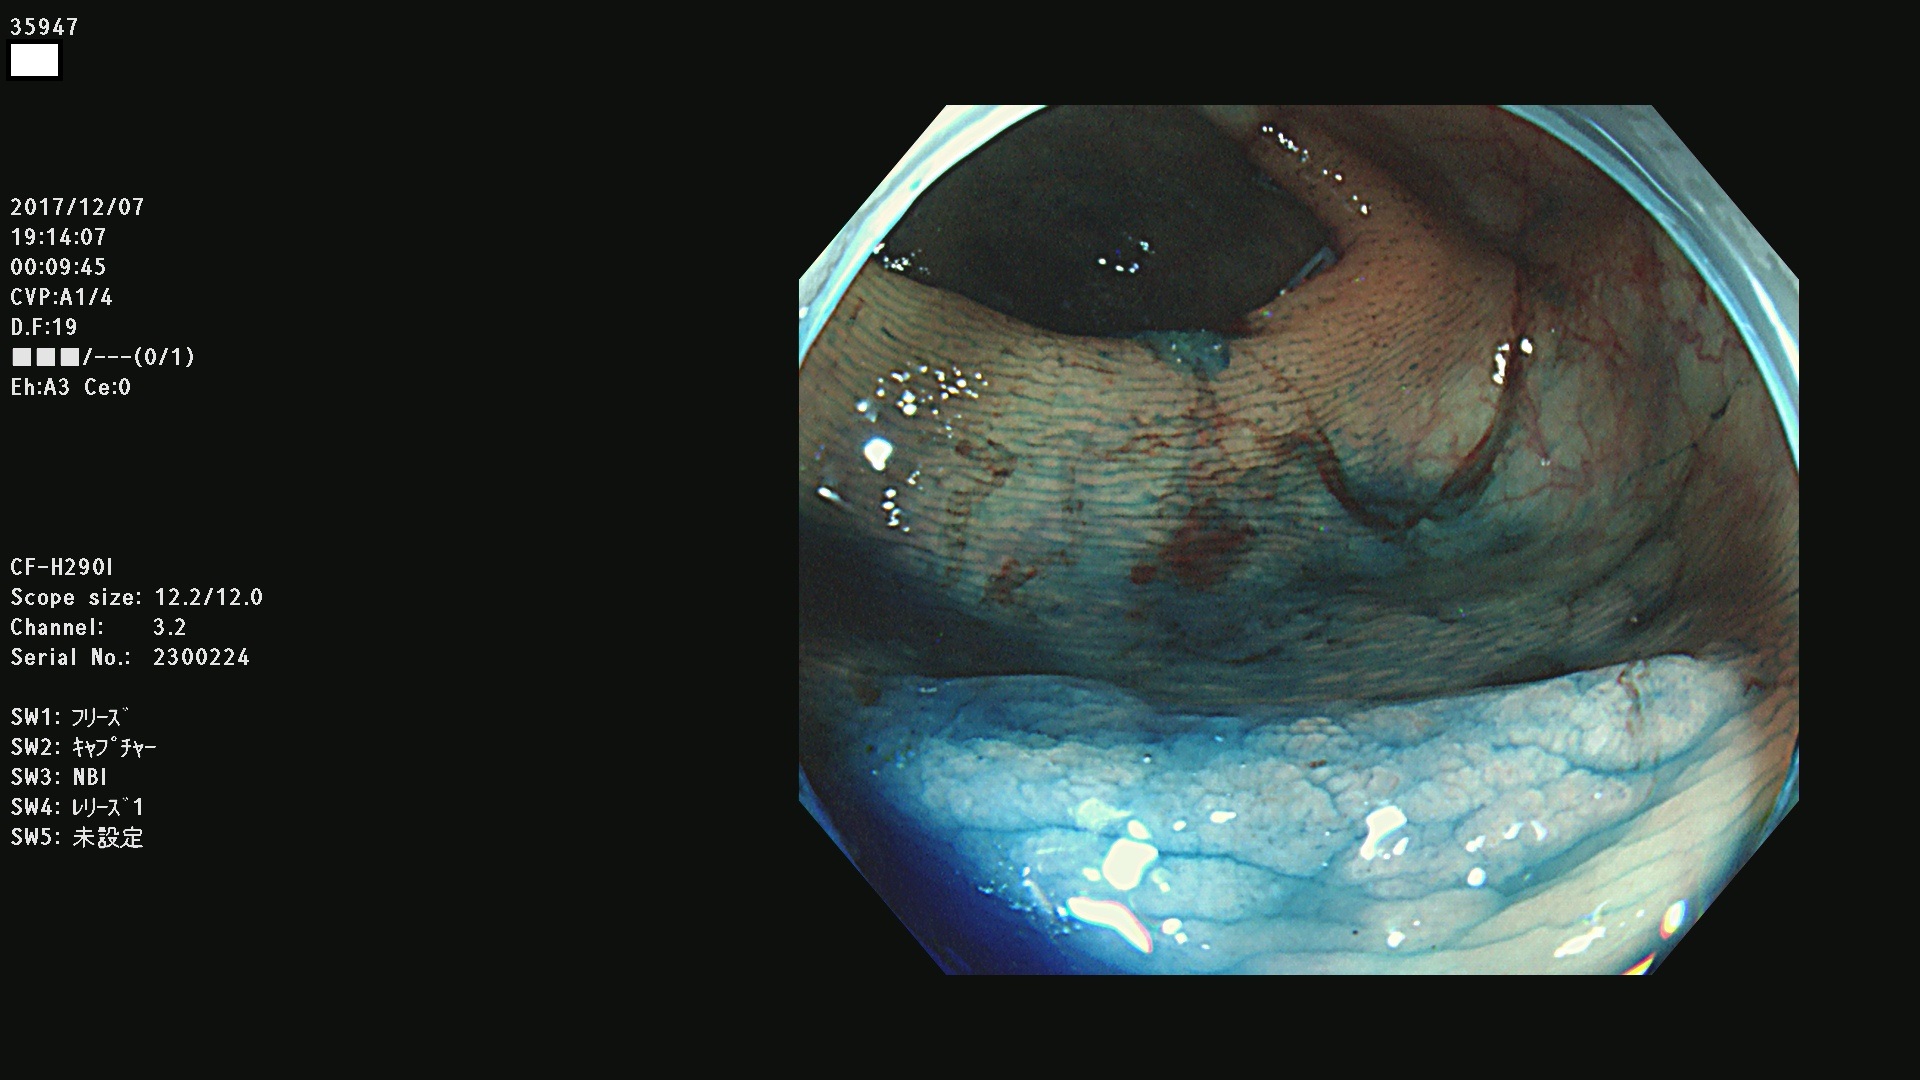

腺腫発見率43 % (カルテ番号 35900〜35999の100名の方の検査結果で集計)大腸癌検診最新情報

以下のカルテ番号の方に腺腫(Adenoma,Group3〜5)が見つかりました(集計法)

35900 35901 35904 35908 35912(SSA/Pのみ) 35914 35918 35922 35925 35926 35928 35931 35932 35933 35934 35937 35939 35943 35945 35947 35949 35951(SSA/Pのみ) 35952 35958 35959 35963 35964(SSA/Pのみ) 35965 35970 35972 35976(SSA/Pのみ) 35977 35978 35979(SSA/Pのみ) 35980(SSA/Pのみ) 35982 35983 35985 35991 35993 35995 35997 35999

発見困難で危険性の高い平坦型病変(上記100名より抽出) ![]()